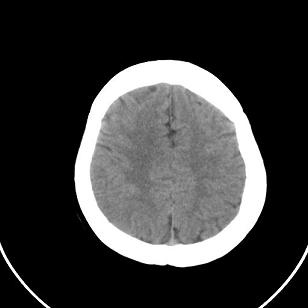

1)脑灰质异位。2)双侧枕部颅骨内板下方类似扇形及弧形脑脊样低密度影;鉴别于巨大枕大池与蛛网膜囊肿之间。建议必要时行进一步检查。